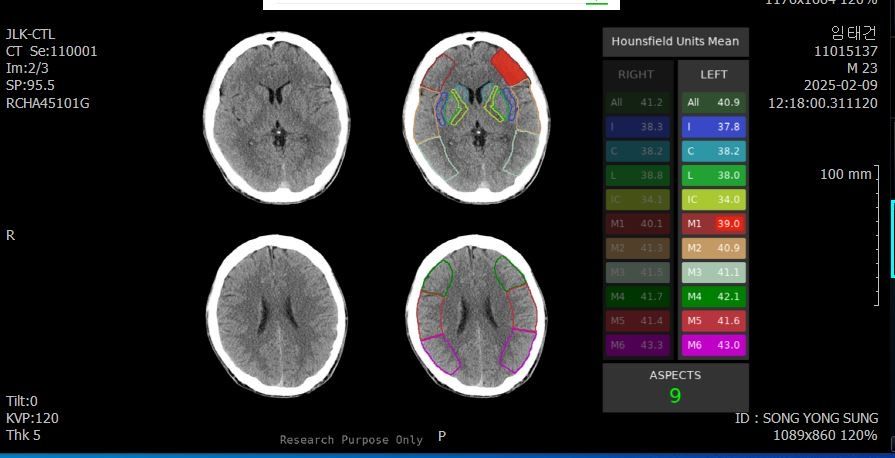

두개골 수술 또는 골절 의심되는 상황인데 엑스레이와 ct사진을 한번 봐주실 수 있나요?

2~3일 정도 기억이 없었는데 그때 머리를 다쳤는지 바로 x-ray와 ct를 찍어봤는데 한번 봐주실 수 있을까요? 진단 목적이 아닌 확인 목적입니다

빨갛게 동그라미 친 곳은 금속물질이 의심도는 부근입니다

• 2번 째 사진